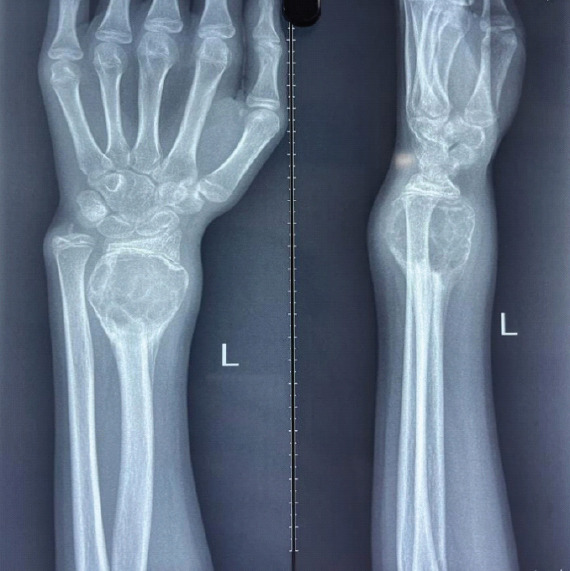

Case report: This case report describes a young skeletally immature female presenting with a Campanacci grade 3 GCT of the distal radius, characterized an osteolytic lesion sparing the epiphysis. Following biopsy confirmation, the patient underwent wide local excision of the tumor with ulnar translocation, fixed using a distal radius locking plate to preserve joint integrity. Post-operative rehabilitation included physiotherapy to restore wrist mobility and grip strength.